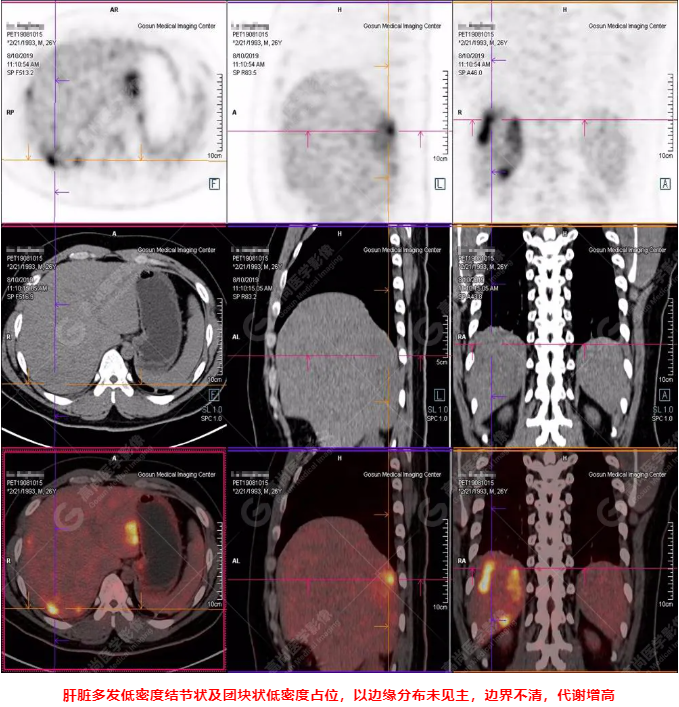

PET/CT全身圖

PET/CT診斷

嗜酸性粒細(xì)胞增多癥肝浸潤

B超及CT檢查發(fā)現(xiàn):肝臟多發(fā)低密度占位。